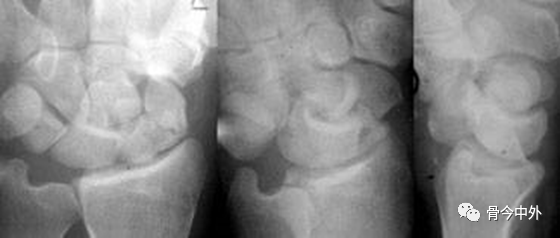

图20 不同体位月骨形状

月骨呈梯形,近侧边缘平行于远侧边缘。月骨若倾斜则呈三角形。仅通过此形状的变化还不能判断月骨是否脱位,因为位置改变,月骨形状也会改变。可能是月骨脱位伴倾斜或仅仅是倾斜。